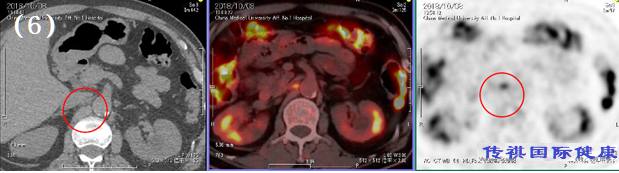

B: 5 . 可见上肠间间膜动脉处右侧大动脉淋巴节的FDG集聚。淋巴节有转移巢的可能性。

C: 6和7,.在气管分歧周围的淋巴节上可见FDG集聚。淋巴节有转移巢的可能性。